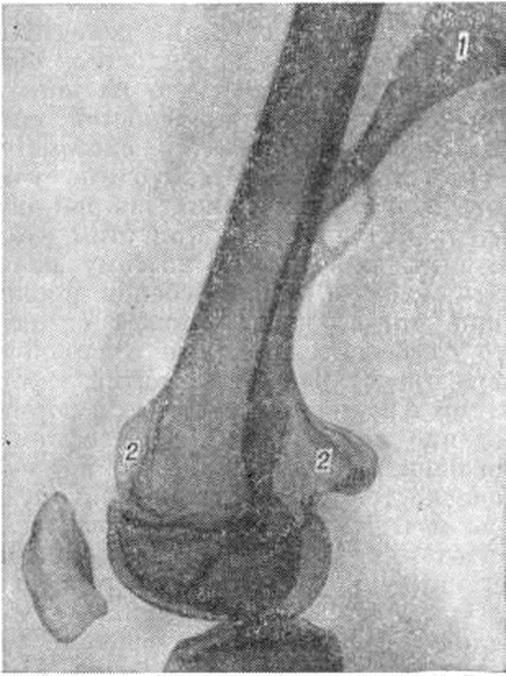

Рис. 9.

Рентгенограмма дистальной трети бедренной кости больного экзостозной хондродисплазией (боковая проекция): множественные экзостозы (1 — линейный, 2 — холмовидные).